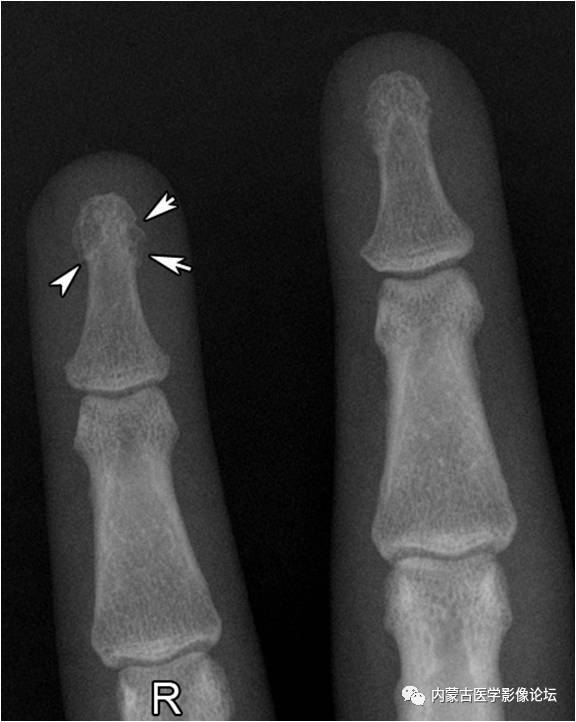

正常指骨粗隆:环指远节指骨粗隆呈不规则分叶状(白箭),部分呈透亮线改变(箭头),但边缘清晰,轮廓线连续,不应误为骨折线或病理改变。